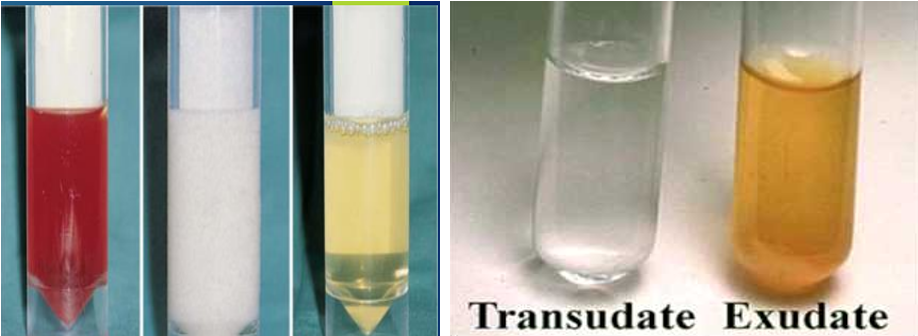

Transudate vs Exudate

Transudate: Fluid permeates into the pleural cavity through intact pulmonary vessels (e.g., in congestive heart failure).

Clear, extravascular fluid caused by:

- Increased capillary hydrostatic pressure (CHF)

- Decreased capillary oncotic pressure (hypoalbuminemia).

- Low in protein and cells.

Common causes

- Congestive heart failure

- Hepatic cirrhosis

- Nephrotic syndrome

- Protein-losing enteropathy

- Hypo-albuminemia

Exudate: *Fluid escapes into the pleural cavity through lesions in blood and lymph vessels (e.g., due to inflammation or tumors). Yellow/cloudy extravascular fluid caused by:

-

Increased capillary permeability (inflammation or malignancy).

-

High in protein and cells.

-

Common:

- Bacterial pneumonia (parapneumonic), empyema, TB

- Carcinoma of the bronchus, lymphoma

- Pulmonary infarction

- Exudates have a protein level of >30 g/L, transudates have a protein level of <30 g/L

- If the protein level is between 25 and 35 g/L, Light’s criteria should be applied.

The BTS recommend using the criteria for borderline cases:

exudates have a protein level of >30 g/L, transudates have a protein level of <30 g/L

if the protein level is between 25-35 g/L, Light’s criteria should be applied. An exudate is likely if at least one of the following criteria are met: